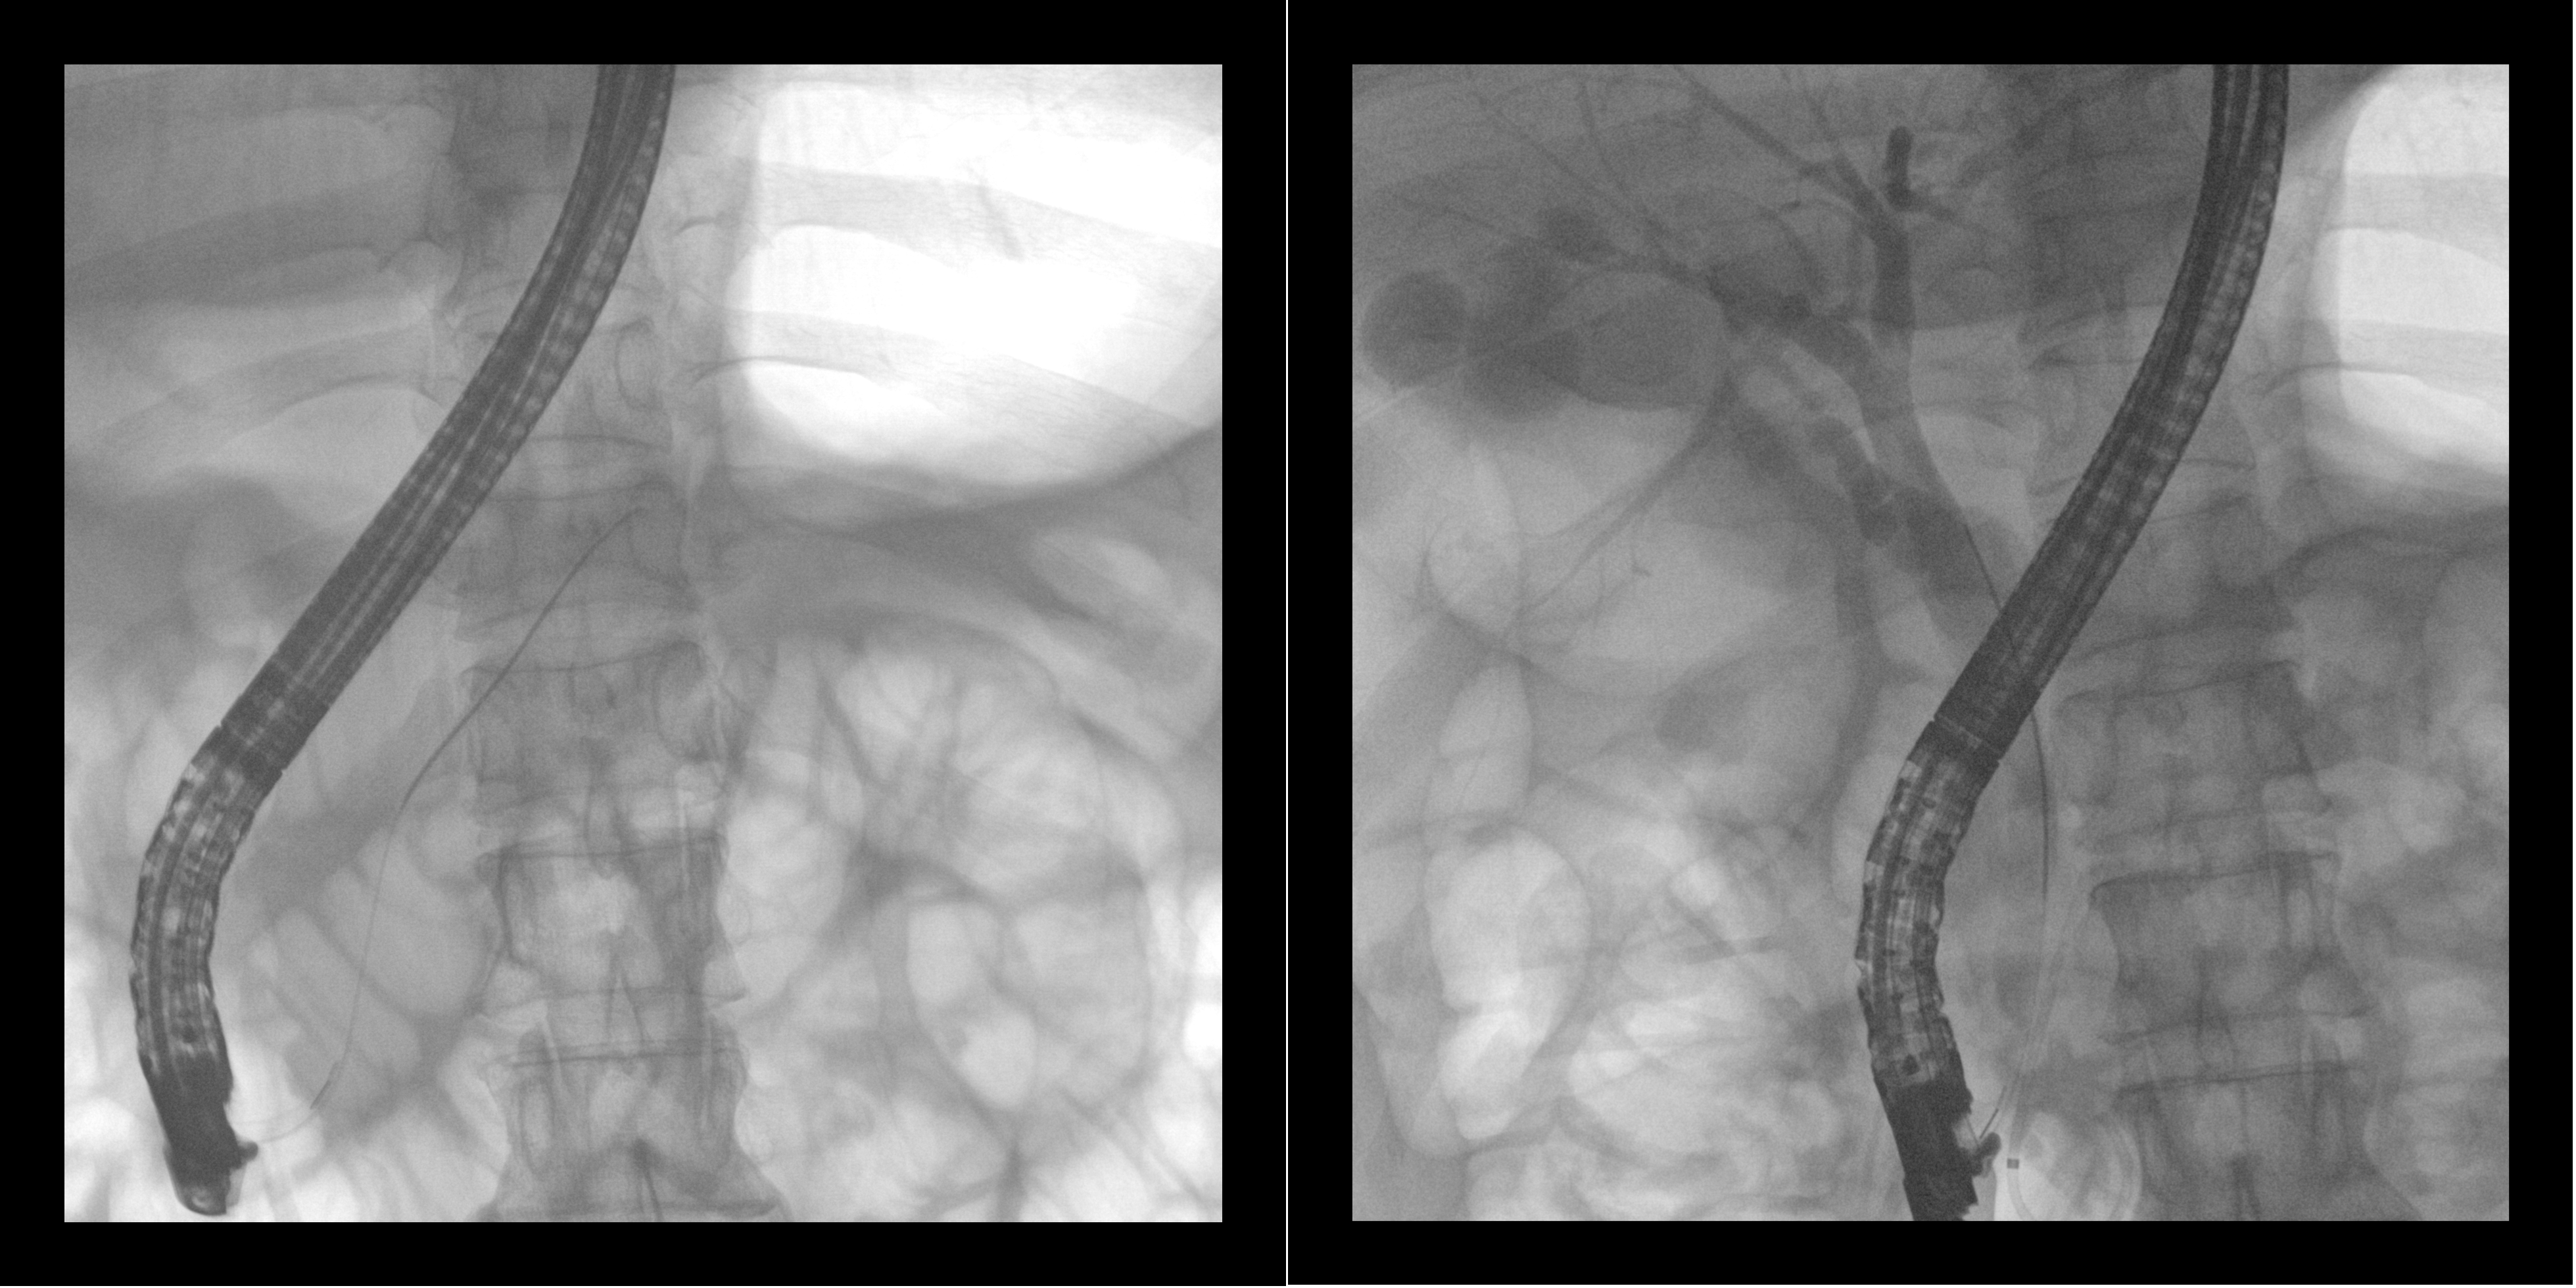

Intraoperative ERCP images

The flat-panel interventional C (PLX7100A) launched by Perlove Medical can cooperate with endoscopy to provide high-definition images and real-time monitoring for ERCP surgery, which can help doctors better understand the condition of the lesion site, so as to better choose the treatment method and operation mode.

01 Large flat panel Wide field of view: 30cm*30cm large-size flat panel detector can provide a larger field of view for surgical observation, enabling the doctor to comprehensively observe the tissues around the stone, making the surgery more efficient and accurate.

02 Outstanding image: Perlove medical flat-panel interventional C can provide high-definition clinical images to help the doctor more accurately determine the location, size and shape of the lesion, to protect the precise operation.